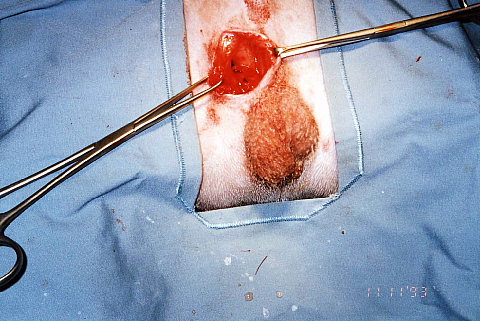

最後は会陰ヘルニアです。

老齢のオス犬によく見られます。

大体は前立腺肥大に続発することが多いですね。

向かって左側、肛門の横が膨らんでますね。

肛門括約筋と尾、後ろ足の筋肉の継ぎ目が裂けて起こります。

裂け目に指を入れてみました。

この症例は発症してから時間があまり経っていなかったので筋肉がしっかり残ってましたのでそのまま裂け目を縫合しました。

時間が経っている時には筋肉が薄くなってそのままでは縫合できないこともあります。

と言うか、そっちのほうが多いですね。

その場合は、色々な方法があるのですが、当院ではシリコンプレートを装着することが多いですね。

白く見えているのがシリコンプレートです。